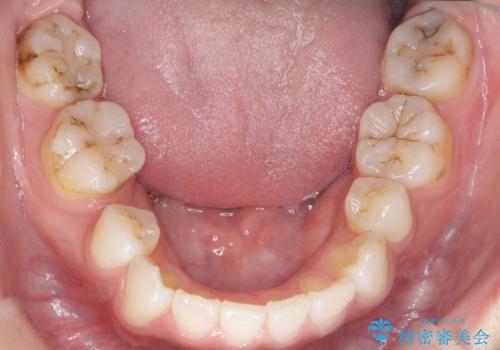

- 奥歯の隙間を治したいとご希望された患者様です。

学生時代に舌側矯正されていたものの、通院が大変になり治療を途中でやめてしまい、奥歯の間に隙間が残ってしまったそうです。

矯正せずに早く治したいという強いご希望とう蝕があることから、セラミッククラウンによる補綴治療で隙間を閉じることにしました。